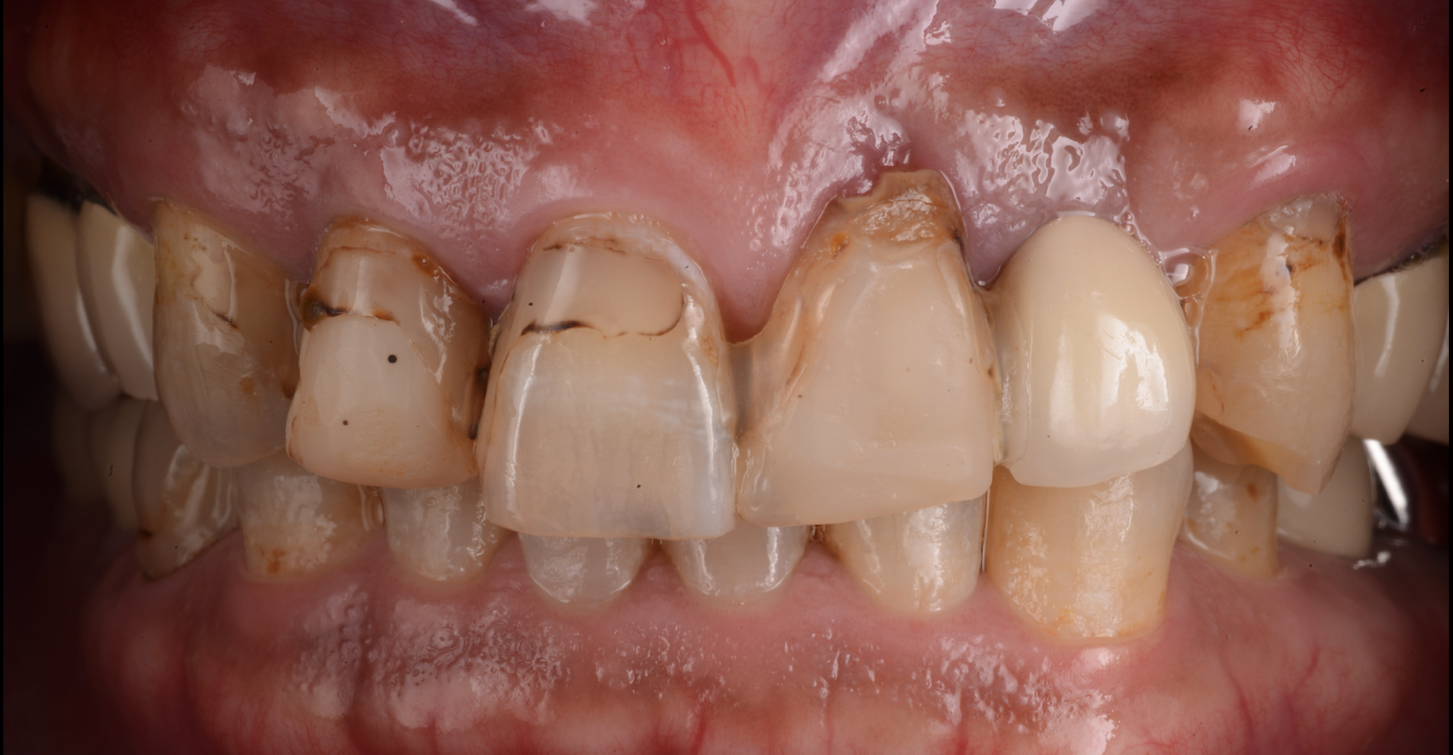

上唇の腫脹を認め、CT検査にて根尖部に嚢胞様透過像を認めた。左上の前歯が不自然に大きく噛み合わせが強くなっていたことがフレアアップの一因と考える。精密根管治療を行い、感染経路を遮断したのち歯根端切除術にて嚢胞を摘出した。

治療前